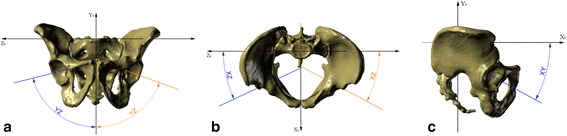

Three sets of reference planes were considered: the plane recommended by the Standardization and Terminology Committee of the International Society of Biomechanics (STC plane) (Figure 2a) [27]; the anterior pelvic plane (APP) described by Robinson and Lewinnek (Figure 2b) [15,18-21,28-30]; and planes established with the use of the sacral base (SB) (Figure 2c). The APP is a commonly used reference plane for the assessment of acetabular cup orientation after total hip replacement [31]. However, there is no consensus as to the reliability of this method for acetabular orientation [18-20,22]. The STC plane is part of the joint coordinate system and is set as a reference plane for reporting hip joint motion [21,27].

Figure 2.

Planes of reference for measurement and pelvic XYZ coordinate system. (a) Recommended by the STC; (b) anterior pelvic plane; and (c) the sacral-base plane, recommended by the authors of this research; each picture with visualization of pelvic XYZ coordinate system. 2D, two-dimensional; 3D, three-dimensional; STC, Standardization and Terminology Committee of the International Society of Biomechanics.

The reference planes adopted in the present study are established by the sacral base (SB, Figure 2c). The horizontal plane of reference is defined as a plane interpolated from the mesh points located on the surface of the SB (the basic assumption was to have at least 30 points; however, we used a mesh with a density of 3 × 3 mm that always gives no less than 100 points and usually over 150 points). The vertical plane is perpendicular to the horizontal one and coincides with the geometric center of the SB (which is automatically set based on the previously applied mesh of points) and the midpoint of a line connecting the centers of the pubic tubercles, which were set based on a minimum of 30 points (mesh of points set on those surfaces at a density of 1 × 1 mm, usually yielding about 100 points) marked on each pubic tubercle surface. This method of plane selection led to the determination of the pelvic XYZ coordinate system (Figure 2c) with the following components: 00: the pelvic origin point (0,0,0) coincident with the geometric center of the SB; X0: the axis formed by the intersection of the sagittal and horizontal planes, pointing anteriorly; Z0: the axis orthogonal to the X0 axis and lying on the horizontal plane, pointing to the right or left depending from the hip joint being evaluated; and Y0: the axis perpendicular to both the X0 and Z0 axes, pointing cranially.